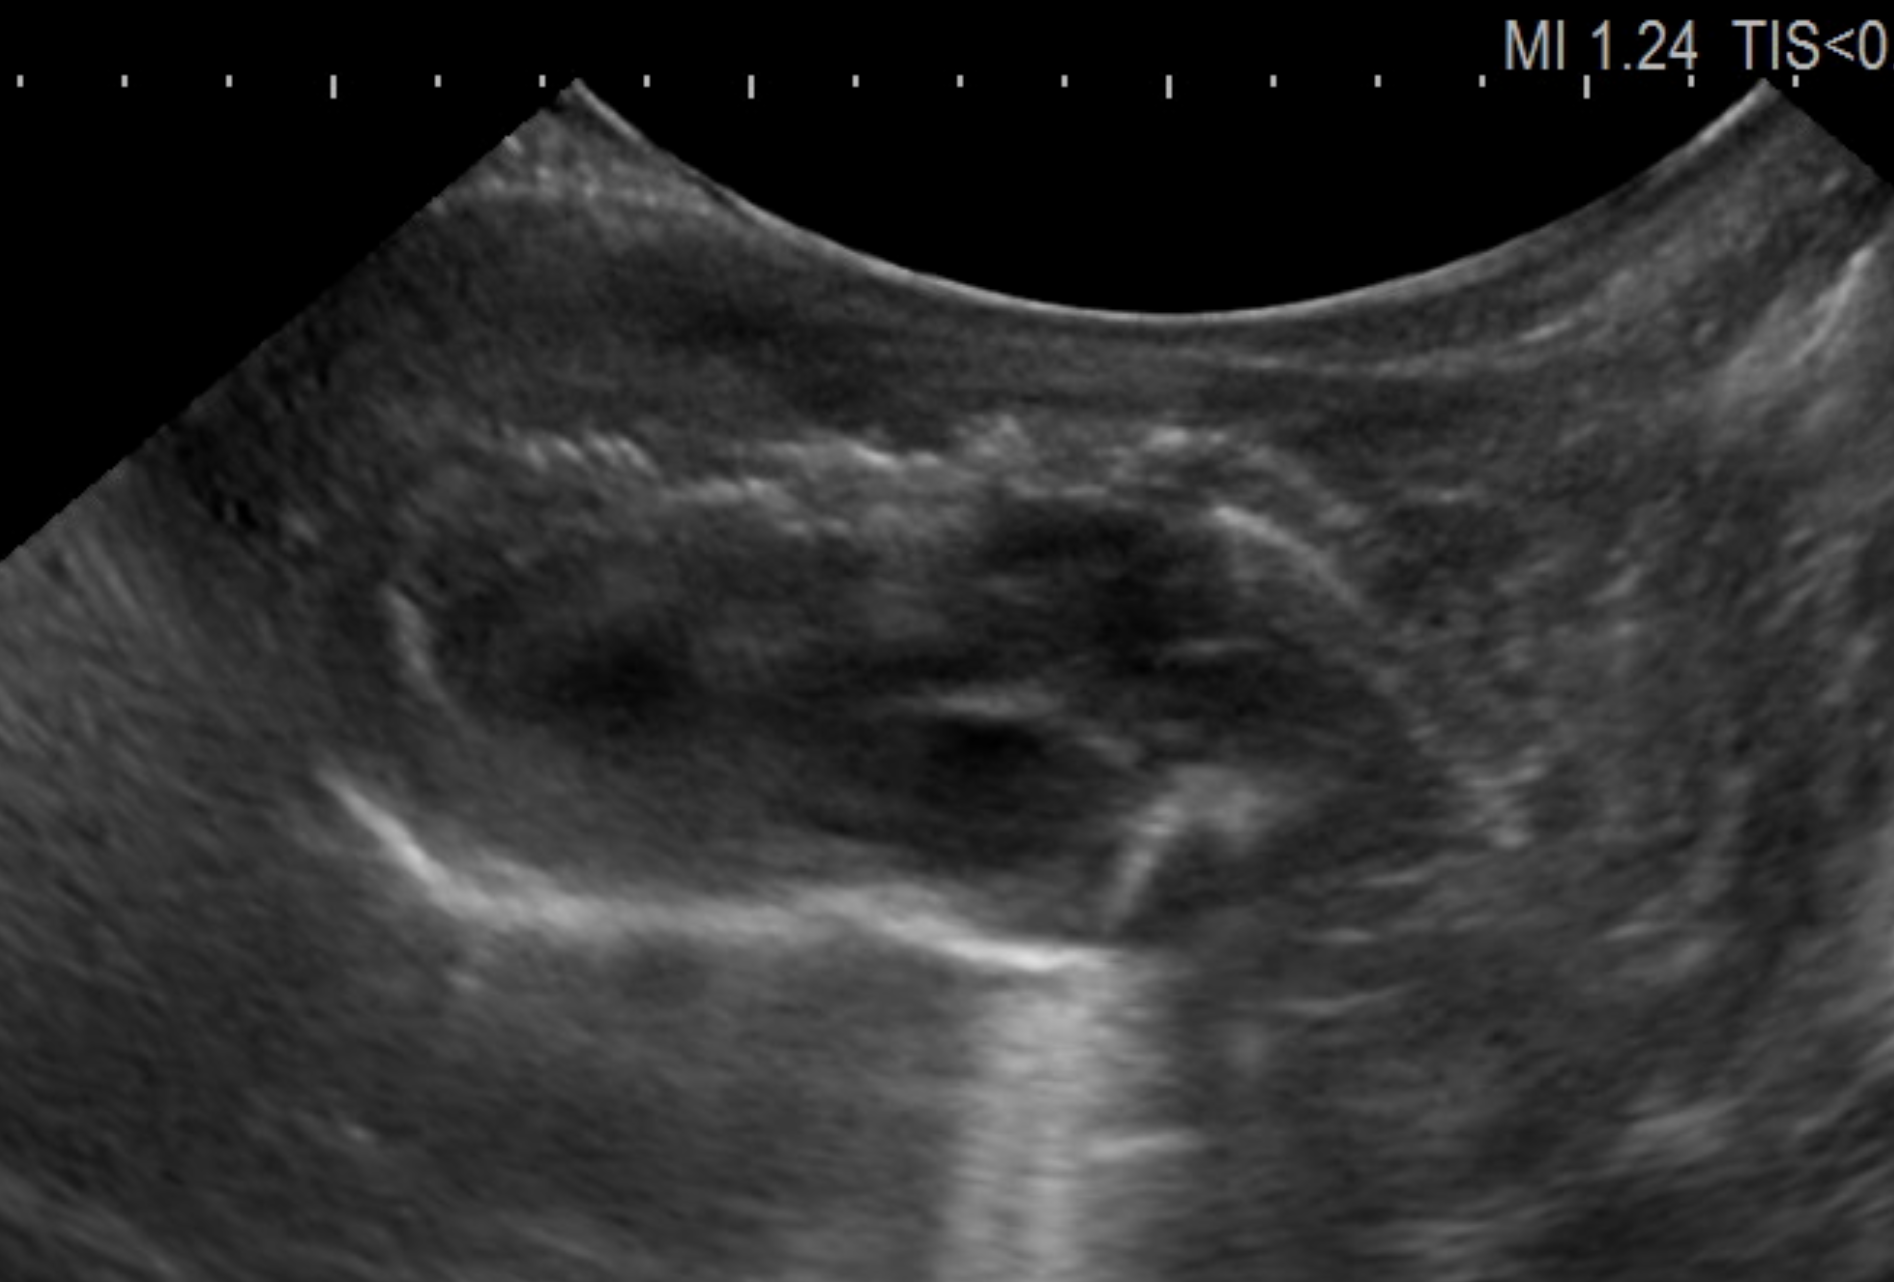

犬や猫では心臓病の診断に欠かせない超音波検査ですが、当院ではハムスターの心臓の評価も同様に超音波検査で行なっています。

画像は拡張型心筋症の1歳8ヶ月ゴールデンハムスターの心エコー画像です。

拡張型心筋症のエコー画像

正常な若いハムスターのエコー画像

比較のため同じく正常のゴールデンハムスターのエコー画像と見比べてもらうと一目瞭然で、心臓の内腔が拡張して見えるのがわかるかと思います。

左心房内に血栓(画像)が確認されることも珍しくありません。